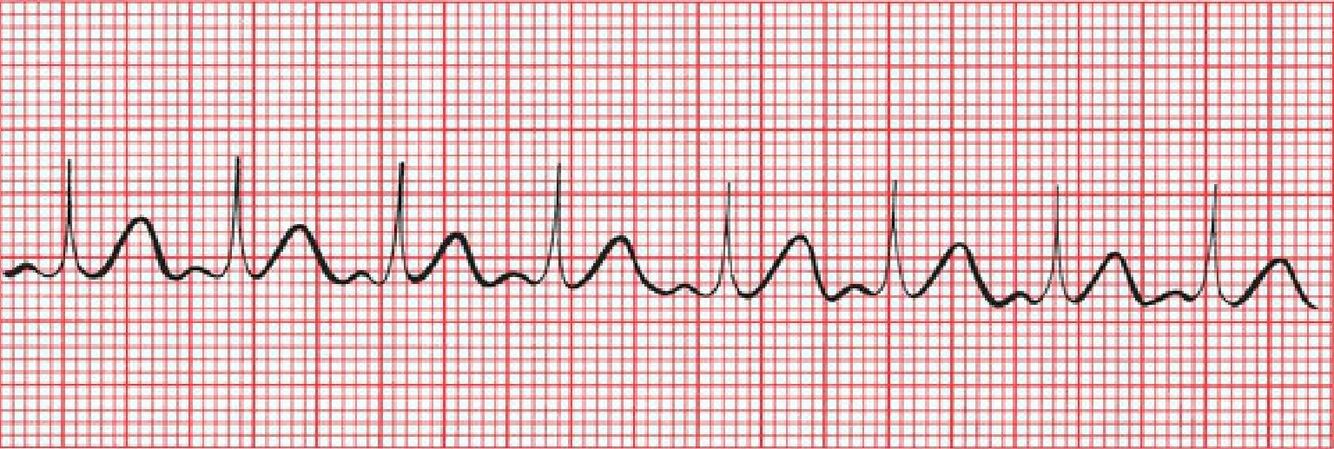

What does this picture illustrate?

Sinus arrhythmia. The heart rate accelerates with inspiration and slows with expiration.